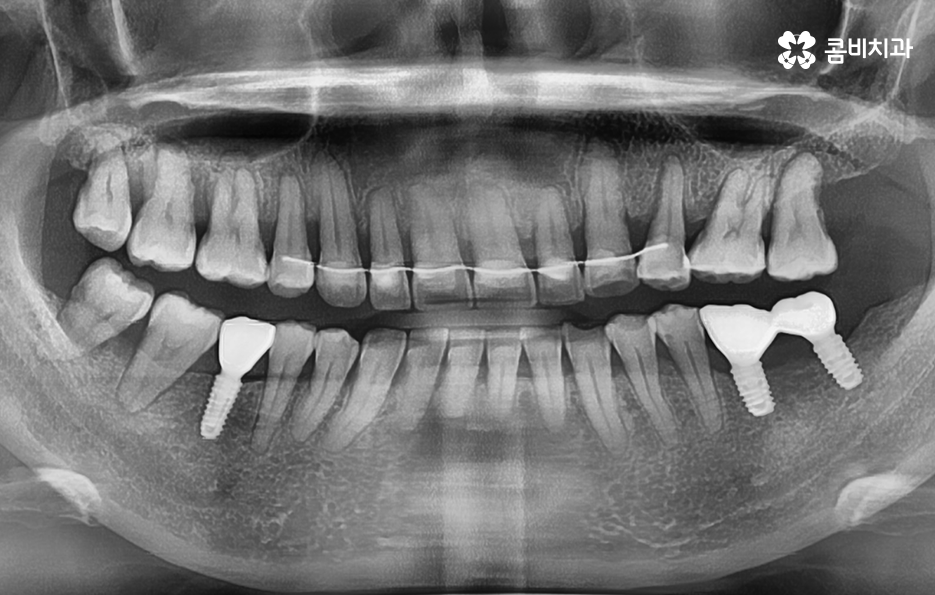

특히 치아가 벌어지거나 삐뚤한 경우에는 임플란트 시술만 한다고 가정할 때 기존의 치열에서 교합 관계 위주로 임플란트의 식립 각도와 위치, 보철물의 크기 등을 결정하게 되지만 치아교정을 통해 가지런한 치열로 개선한 후에 임플란트를 식립하는 경우에는 가지런한 치열을 갖춘 상태에 적합한 임플란트 치료 계획을 세운다는 점에서 이점이 있어요

오늘 보시는 포스팅에서의 치료 과정도 어금니에 임플란트가 필요한 상태에서 윗니를 보시면 윗니가 다소 벌어진 것을 확인할 수 있는데요. 교정 하면 보통 전체교정을 떠올리게 되긴 하지만 경우에 따라서는 치열이 전체적으로 가지런한 편인데 앞니가 살짝 벌어진 경우나 어금니만 다소 벌어진 경우도 있을 거예요

이러한 경우에는 부분교정을 통해서 다소 개선이 필요한 치열을 가지런하게 만들고 가지런해진 치열과 교합 상태에 적합한 임플란트 치료 계획을 세워서 치아의 심미성과 기능적인 부분, 얼굴과의 조화를 종합적으로 고려하여 좋은 결과를 얻을 수 있어요

이처럼 임플란트를 할 계획이거나 이미 했어도 치아교정이 가능한 사례가 많다는 점에서 너무 걱정하기 보다는 정밀 검진과 교정 전문의와 충분히 상담 후에 판단해보시길 바라며 가지런한 치열은 심미적인 부분이 아니더라도 치아의 저작 기능과 청결 관리에서도 중요한 부분이니 임플란트와 치아교정을 동시에 진행도 가능하다는 점 알아두시면 좋을 거예요